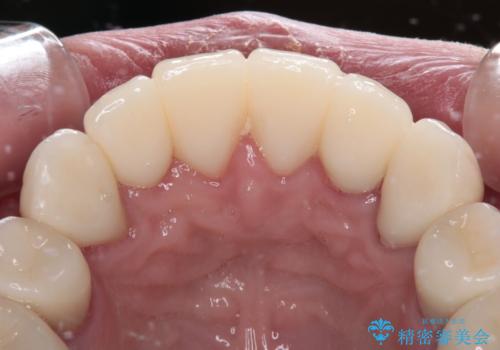

矯正治療終了後に、残った歯をオールセラミッククラウンにて補綴治療を行うこととしました。

途中来院が困難な時期があったり、歯周外科処置を行って治癒を待ったりと、治療期間は長くなりましたが、初診時とは比べものにならないくらいきれいに仕上げることができました。